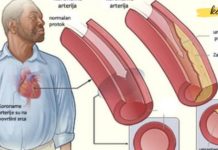

The warming effect combined with the anti-inflammatory properties of camphor and ammonia penetrates deep into tissues, easing joint stiffness and pain.

Coarse salt is known for its detoxifying and circulation-stimulating properties. It helps to draw out impurities and reduce swelling when applied topically.

Camphor alcohol provides a cooling and warming sensation, stimulates blood flow, and is widely used in many traditional remedies for its analgesic (pain-relieving) and anti-inflammatory effects.

Ammonia has long been used in traditional medicine as a rubefacient—meaning it increases blood flow to the applied area, which helps relax muscles and ease joint stiffness.